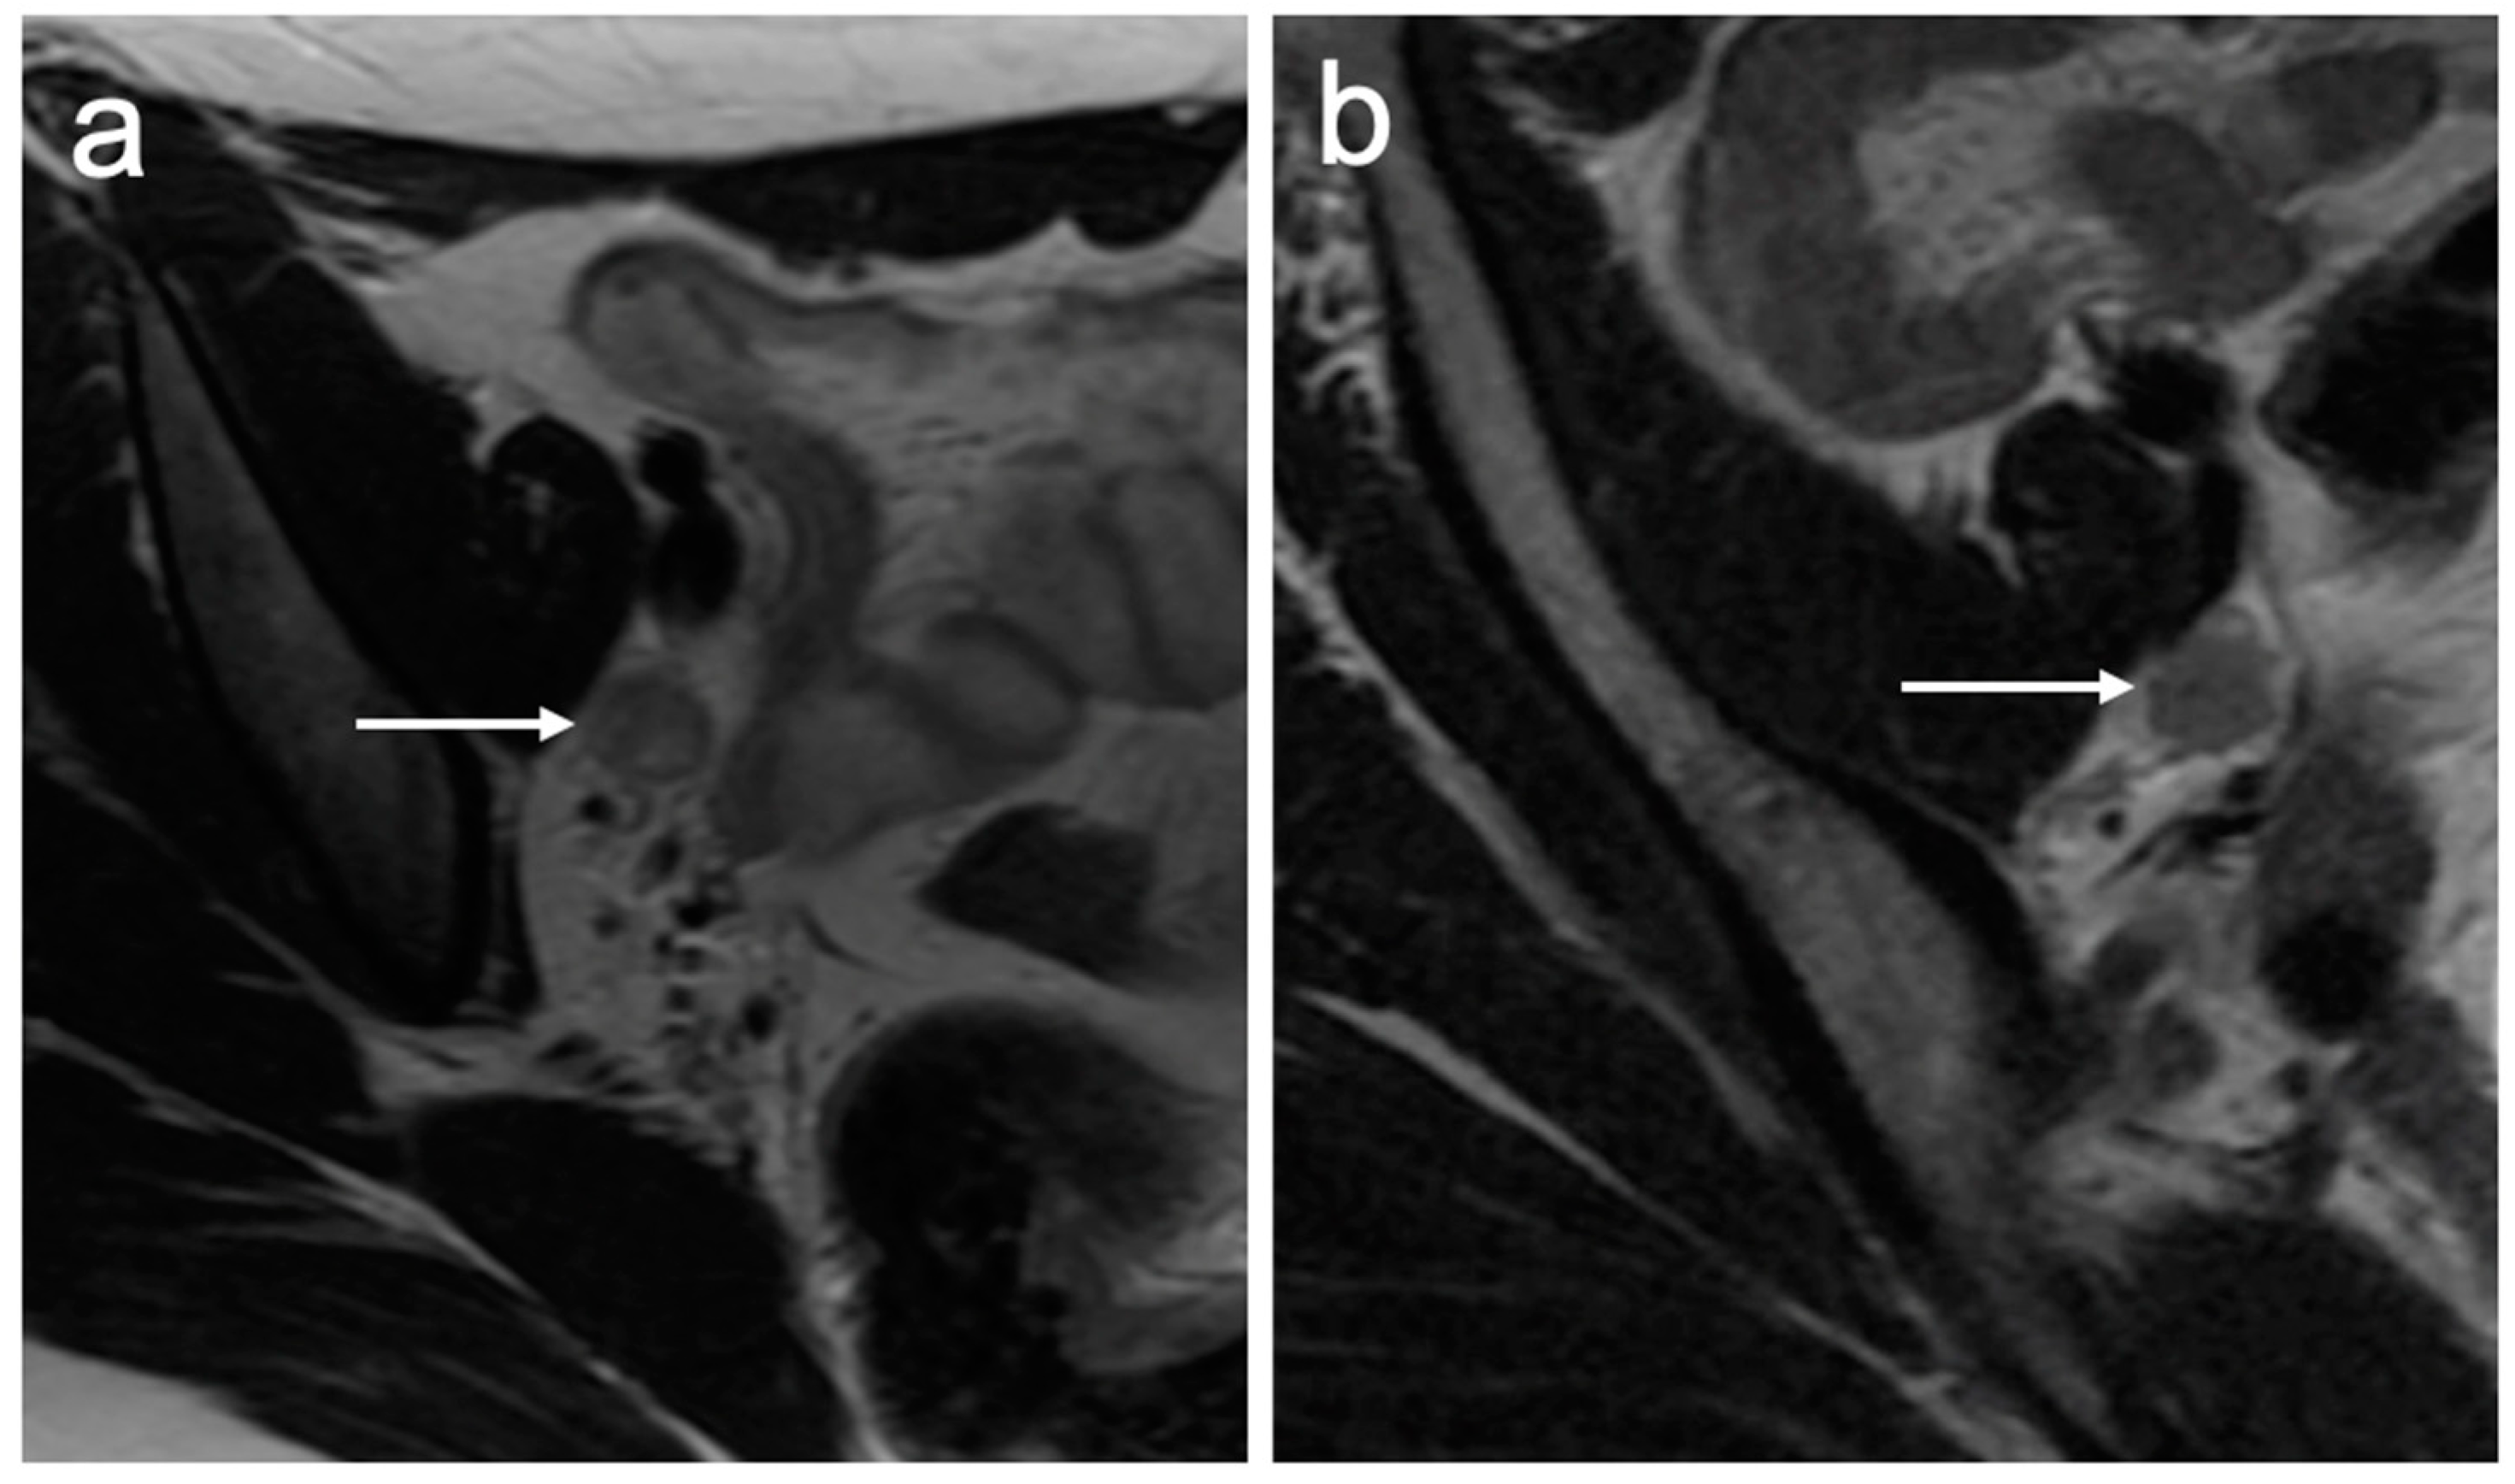

- Valentini, A.L.; Gui, B.; Miccò, M.; Giuliani, M.; Rodolfino, E.; Ninivaggi, V.; Iacobucci, M.; Marino, M.; Gambacorta, M.A.; Testa, A.C.; et al. MRI anatomy of parametrial extension to better identify local pathways of disease spread in cervical cancer. Diagn. Interv. Radiol. 2016, 22, 319–325. [Google Scholar] [CrossRef]

| IIB | With parametrial invasion but not up to the pelvic wall |